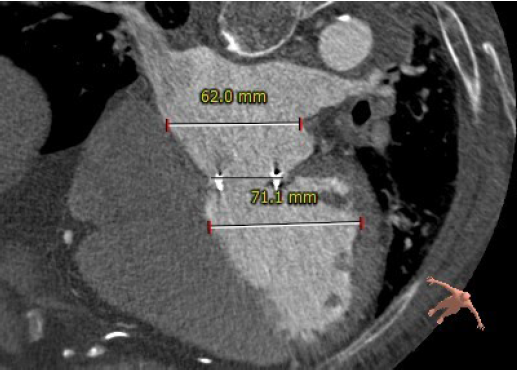

术前CT评估

生物瓣瓣环内径23.5mm

生物瓣瓣环外径29.5mm

生物瓣环周围无明显钙化

生物瓣瓣架高度16.1mm

左房及左室内径

主动脉与生物瓣轴夹角76°

左室与生物瓣轴夹角145°